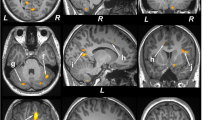

Multiple brain areas showed reduced regional gray matter volume in T2DM compared to control subjects (Fig. 1; covariates, age and sex), including the bilateral prefrontal cortices (a, c), para-hippocampal gyrus (k), cerebellar cortex (i, j), vermis, brainstem, and bilateral cerebellar tonsil. The decreased gray matter volume was remarkable for the bilateral anterior (l, m) and posterior insular cortices, anterior (d), mid (f), and posterior (e) cingulate gyri, hippocampus (b), amygdala (n), caudate, basal-forebrain, thalamus, putamen, lingual gyrus (g, h), bilateral pre- and post-central gyrus, inferior, mid (o) and superior frontal cortex (p), inferior, mid, and superior occipital, superior parietal, and inferior (r), mid (q), and superior temporal gyrus. None of the brain regions showed increased gray matter volume in T2DM compared to control subjects. The regional brain gray matter volumes of T2DM and control subjects and effect sizes are tabulated in Table 2.

Brain regions with reduced gray matter volume in T2DM patients over controls after controlling for age and sex (FRD corrected, p < 0.01). These sites with reduced gray matter volume included the bilateral prefrontal cortices (a,c), right hippocampus (b), left anterior (d), mid (f) and posterior (e) cingulate, bilateral lingual gyrus (g,h), bilateral cerebellar cortices (i,j), right parahippocampal gyrus (k), bilateral anterior insula (l,m), right amygdala (n), right mid (o) and left superior (p) frontal cortices, right inferior (r) and mid (q) temporal gyrus. All images are in neurological convention (L = left; R = right). Color bar indicates t-statistic values.